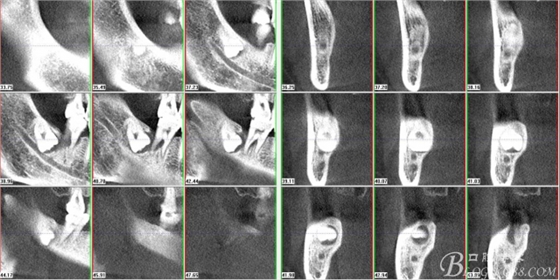

圖3.通過(guò)矢狀面和冠狀面來(lái)判斷48與下頜管及47的關(guān)系

圖4.水平方向48與47之間的關(guān)系

圖5. 48的三維視圖

圖6.測(cè)量48頰、舌側(cè)骨板厚度。

圖7.測(cè)量牙冠近遠(yuǎn)中徑的大小及遠(yuǎn)中骨板的厚度